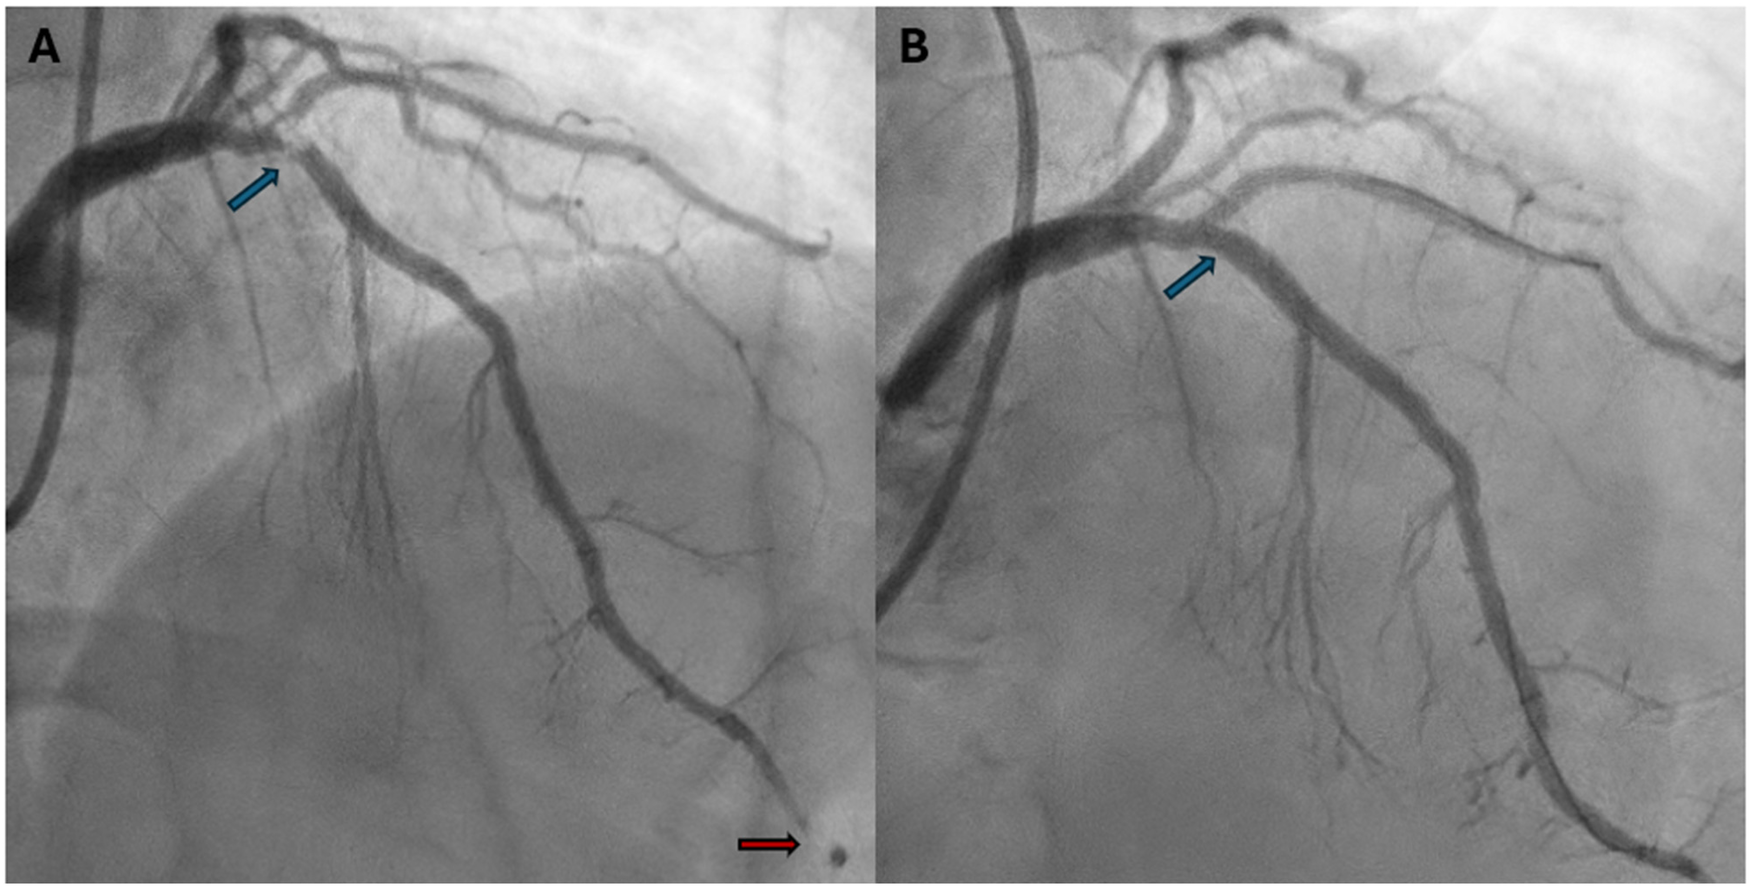

Due to the persistence of epigastric pain, a 12-lead electrocardiogram (ECG) was performed (Figure 1A), showing sinus rhythm at 75 bpm with 1.5 mm ST-segment elevation in leads V5 and V6. Bedside echocardiography showed a mild reduction of left ventricular ejection fraction (LVEF) of 45%, left ventricular apical akinesia, and hypokinesia of the mid-to-distal anterior and anterolateral segments. No significant valvular abnormalities or pericardial effusion were found. A diagnosis of STEMI was made, and the patient received an aspirin loading dose of 250 mg and ticagrelor of 180 mg. Emergency coronary angiography showed a thrombotic sub-occlusion of the left anterior descending artery (LAD) involving the ostium of D1, patency of the previously implanted stent to D1 without restenosis (Figure 2A), and a spontaneous distal embolization defect of the apical LAD with thrombolysis in myocardial infarction (TIMI) 1 flow. Manual thrombus aspiration was performed to the LAD lesion at the level of the bifurcation with D1 only. It was not attempted at the very distal apical LAD because of the small caliber of the vessel. A residual tight stenosis of the LAD at the bifurcation level was treated with a 3.5 × 18 mm DES implantation to the LAD, kissing balloon inflation (3.0/2.0 mm) to LAD-D1, and the final proximal optimization technique with a 3.5 mm NC balloon. Post-procedure echocardiography showed an LVEF of 40%, with akinesia of the apex and of the mid-to-distal anterior and anterolateral segments, without evidence of mechanical complications. Blood examinations showed a peak value of hs-TnI of 19.980 ng/L at 32 h. Continuous ECG monitoring recorded frequent premature ventricular contractions and a brief episode of non-sustained ventricular tachycardia. Therefore, beta-blocker therapy with intravenous metoprolol was started. However, shortly after drug administration, the patient experienced a transient episode of epigastric pain that was responsive to sublingual nitroglycerin. In suspicion of drug-induced vasospasm, metoprolol was promptly discontinued with no symptom recurrence. Heart failure medications including an ace-inhibitor, a mineralocorticoid receptor antagonist, and a sodium-glucose co-transporter 2 inhibitor were started and well-tolerated. On day 3 following the index procedure, cardiac magnetic resonance imaging showed a moderate LVEF reduction (38%), akinesia in the anterior and anterolateral mid-apical regions with apical thrombosis (9 × 20 mm), and late gadolinium enhancement (LGE) extension wall thickness >75% in the same regions with wall motion abnormalities (Figures 3A,B). Rivaroxaban at 20 mg daily was started and ticagrelor was discontinued and de-escalated to clopidogrel, which was continued for 1 week after the index procedure. On day 7, the patient was discharged home asymptomatic on dual antithrombotic therapy with aspirin 100 mg daily plus rivaroxaban 20 mg daily. Discharge ECG showed a reduced R wave progression on the anterior leads with resolution of the ST-segment elevation (Figure 1B). At the 3-month follow-up, the patient was free from angina. She is on dual anti-thrombotic therapy with aspirin and rivaroxaban. A cardiac magnetic resonance found an LVEF of 42%, an unchanged LGE pattern, and a significant reduction in LV apical thrombus size (2 × 8 mm).

Figure 2

Baseline and final coronary angiography. (A) Baseline coronary angiography (RAO 30°, cranial 30°) shows a thrombotic subocclusion of proximal LAD with ostial involvement of D1 (blue arrow). The previously implanted DES on D1 is patent and free of restenosis. A perfusion defect in the distal LAD suggests spontaneous distal embolization (red arrow). (B) Final coronary angiography (RAO 30°, cranial 40°) shows a good angiographic result after PCI to LAD-D1 bifurcation with single DES implantation (3.5 × 18 mm) to the LAD, a kissing balloon with NC 3.0/2.0 mm to LAD/D1, and the proximal optimization technique with a 3.5 mm NC balloon (blue arrow). RAO, right anterior oblique; LAD, left anterior descending; D1, first diagonal; DES, drug-eluting stent; PCI, percutaneous coronary intervention; NC, non-compliant balloon.